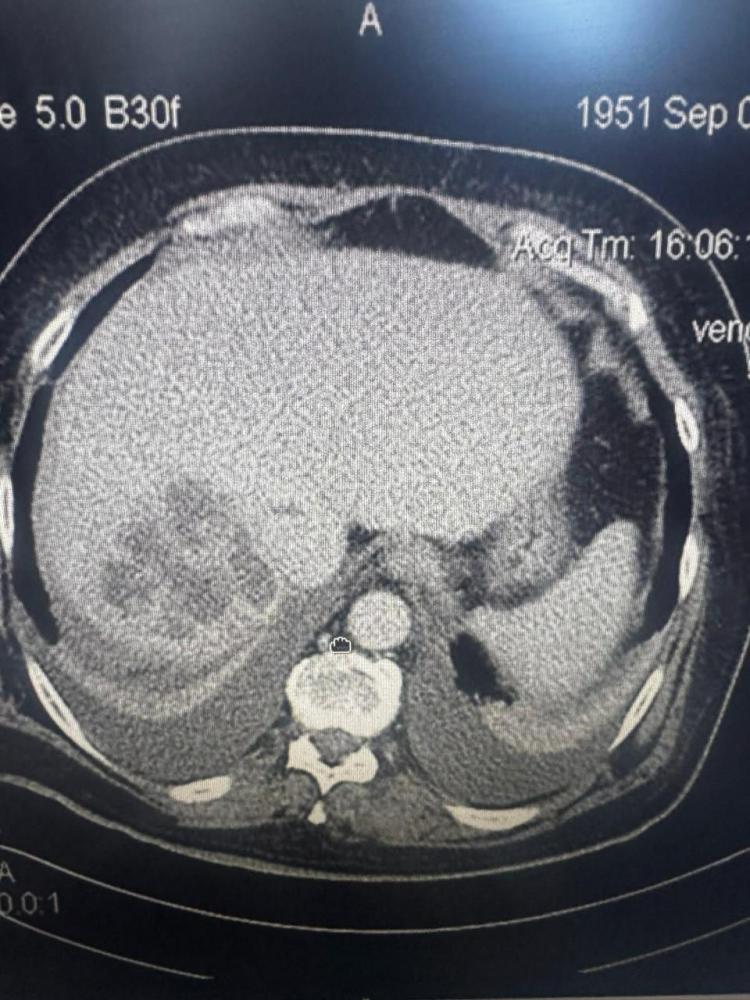

Бригада скорой помощи доставила во Владивостокскую клиническую больницу № 1 53-летнего мужчину, потерявшего сознание от сильных болей в животе. Экстренное УЗИ выявило критическое состояние: огромная киста полностью перекрывала печень и требовала немедленного вмешательства, сообщает РИА VladNews со ссылкой на Минздрав Приморья.

Руководитель отделения общей хирургии Игорь Кондрашов рассказал, что под местной анестезией и контролем УЗИ хирурги оперативно установили дренаж. Из кисты было эвакуировано около двух литров жидкости, после чего в полость ввели специальные склерозирующие препараты, чтобы предотвратить повторное наполнение.